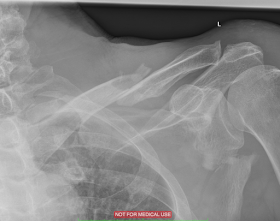

The xrays confirm cracks in my scapula, clavicle and three ribs. You can see the pieces of my clavicle and the gaping fissure in my scapula. But that does not seem to be at an important junction of forces. I continue to improve. I can lift my left arm high with support.